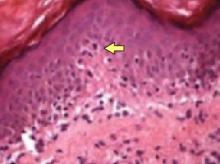

FIGURE 3

Hematoxylin/eosin stain

Hematoxylin and eosin stain (at 400× power) of punch biopsy showing “cerebriform” lymphocytes at the dermal-epidermal junction, migrating into the epidermal layer.